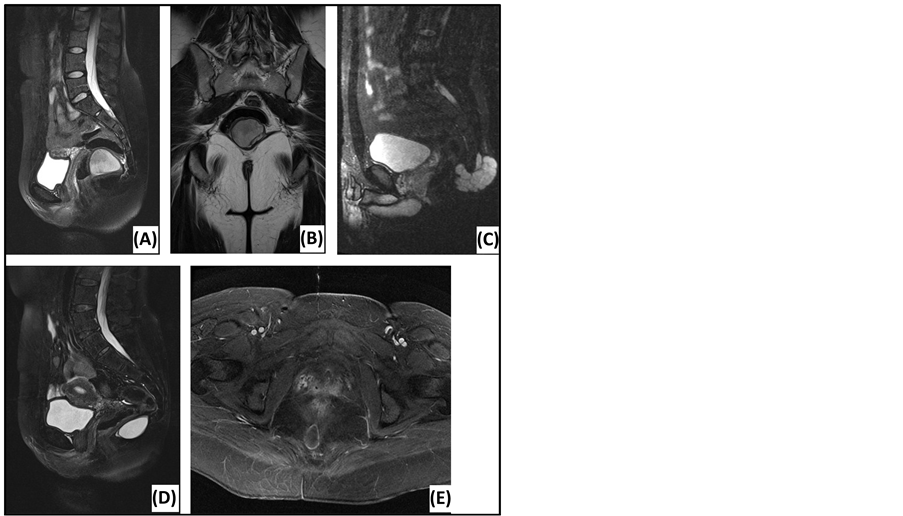

Preoperative work-up was done by MRI. Findings are summarized in Table 2 and propose a broad differential diagnosis. Examples are shown in Figure 2. Two diffusion-weighted MRI’s (DWI) were performed, using apparent diffusion coefficient (ADC) values at low (0 s/mm2) and high (1000 s/mm2) diffusion gradients. ADC values were high for both diffusion gradients (Figure 3). Five patients underwent computed tomography (CT) before MRI. Other technical investigations before MRI or CT included a positron emission tomography (PET), a transrectal ultrasonography (TRUS), a transabdominal ultrasonography and two anoscopies. No presacral lesions were found. TRUS illustrated dilated seminal vesicles. Transabdominal ultrasonography suggested acute appendicitis. One anoscopy revealed an anal fissure.

Figure 2. Magnetic resonance imaging of presacral lesions. (A) Sagittal T2-weighted MRI of a tailgut cyst: located below S3, sharp tumor margins, high signal intensity, homogeneous, unilocular. (B) Coronal T2-weighted MRI of a tailgut cyst: external compression of the rectum. (C) Sagittal T2-weighted MRI of a chordoma: located below S3, extension behind the sacrum, sharp tumor margins, high signal intensity, homogeneous, multiple septations. (D) Sagittal T2-weighted MRI of an epidermoid cyst: located below S3, sharp tumor margins, high signal intensity, homogeneous. (E) Axial T1-weighted MRI of an epidermoid cyst: Gadolinium enhancement in the wall of the lesion.

Due to the excellent soft-tissue resolution and multiplanar capacity, MRI is the best imaging modality to assess tumor location, size, morphology and adjacent structures [5] [6] [10] . The risk of malignancy can be estimated based on following features: heterogeneity, solid appearance, irregular or infiltrative borders, variable enhancement after gadolinium administration, rapid growth and extension above S3 [3] [5] [18] . Our findings predicted malignancy with 100% accuracy, confirming the current literature. Biological behavior also correlates with diffusion restriction. DWI can distinguish benign and malignant lesions, using quantitative ADC measurements. Several authors report significantly higher ADC values at high diffusion gradients for benign lesions [31] -[33] . Our findings concur with this conclusion. Specific diagnosis by MRI is difficult. Glasgow et al. report 28% of MRI diagnoses to be in accordance with the histological diagnosis [2] . Radiological evaluation provided a differential diagnosis in order of preference. Accuracy was 57.1%: two epidermoid cysts were mistaken for tailgut cysts and one tailgut cyst was mistaken for endometriosis. Presacral cysts usually have low signal intensity on T1-weighted images and high signal intensity on T2-weighted images. This may be influenced by the cyst’s content: blood, proteins and mucins cause higher signal intensity on T1-weighted images. Fat content is best seen on T1-weighted images using fat suppression. This is suggestive of a dermoid cyst. Tailgut cysts are multicystic, in contrast to other cystic masses. A chordoma is lobulated with a heterogeneous high signal intensity on T2-weighted images and low-intermediate signal intensity on T1-weighted images. Gadolinium injection reveals a heterogeneous enhancement with a honeycomb appearance [5] [18] [34] .